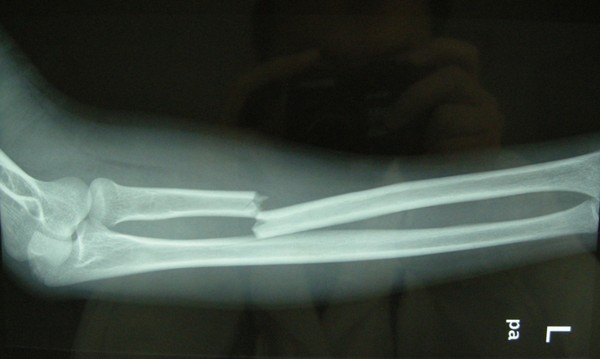

今日,三院骨科專(zhuān)家一一為病人解開(kāi)疑惑,很多骨折病人需要進(jìn)行切開(kāi)復(fù)位內(nèi)固定手術(shù)。但是,骨折通常伴有局部腫脹,這種開(kāi)放性手術(shù)的時(shí)機(jī),要根據(jù)骨折部位的腫脹程度來(lái)確定。有部分病人不理解手術(shù)和消腫之間的關(guān)系,很容易對(duì)醫(yī)生產(chǎn)生誤解。

如果病人骨折處腫得很厲害,一般要先消腫。否則,若強(qiáng)行進(jìn)行內(nèi)固定手術(shù),容易并發(fā)感染。

骨折后的腫脹,通常呈現(xiàn)以下規(guī)律:一般1~3天是腫脹的高峰期,3~5天開(kāi)始消腫,5~7天腫脹消退。有些嚴(yán)重的骨折消腫較慢,可能要花上1~2周。

不同的骨折部位,情況也是不一樣的。例如:肌肉豐富的大腿部位,較輕的腫脹也可以做手術(shù),這是因?yàn)樵撎幖∪獗容^豐富,做完手術(shù)之后軟組織可以覆蓋手術(shù)切口。然而,像小腿的脛骨、足部的跟骨等部位,軟組織較少,屬于皮包骨,倘若腫脹很?chē)?yán)重時(shí)使用鋼板進(jìn)行內(nèi)固定,手術(shù)以后將會(huì)出現(xiàn)軟組織覆蓋不了,皮膚也縫不上的狀況。所以,這些情況必須先消腫再手術(shù)。

隨著相關(guān)知識(shí)的普及,病人也漸漸能理解,腫脹嚴(yán)重卻強(qiáng)行手術(shù),將會(huì)導(dǎo)致皮膚感染、皮膚缺損、鋼板外露和骨髓炎等危害。